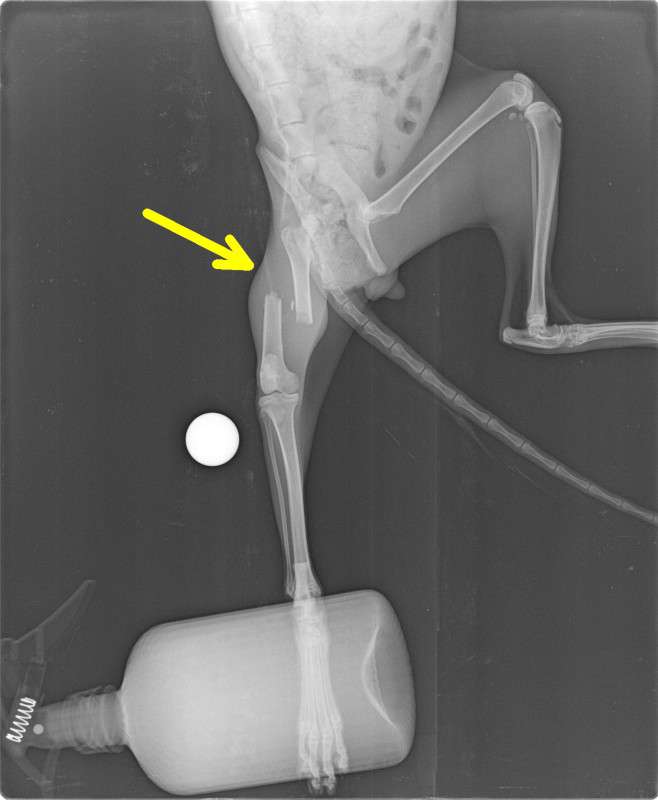

Bewegungsapparat